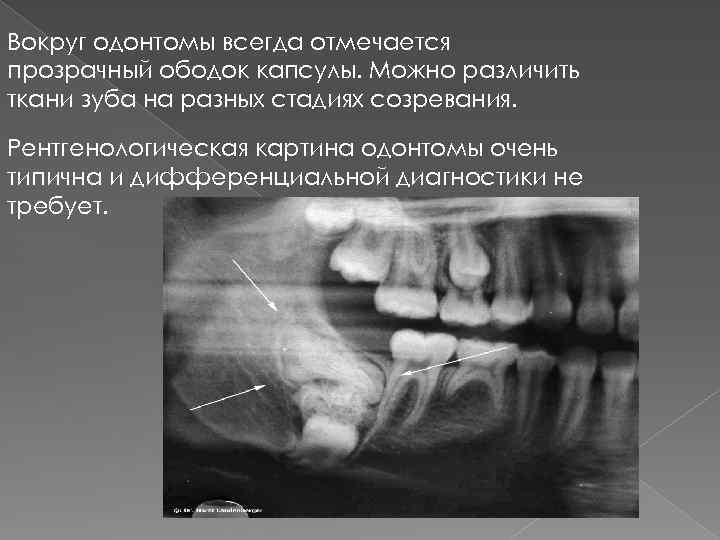

Одонтома нижней челюсти: фотографии и медицинская информация